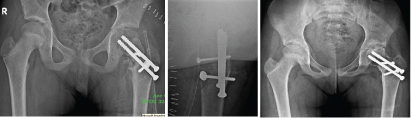

Procedure: Under spinal anaesthesia, child was put on prone position on fracture table and through posterior approach fracture site was exposed. Intraoperatively, we noted sclerosis of the fracture, which was freshened. Fracture was reduced, neck shaft angle was corrected and fixed with two 6.5mm cannulated cancellous screws. The fixation was augmented with quadratus femoris muscle which was elevated with a bone pedicle of length 4cm, width 1.5 cm and depth 1cm from its insertion on the posterior aspect of the femur. The muscle pedicle bone graft was rotated and placed posteriorly over the fracture site and pegged into the trough created in the head and fixed with two 4mm cannulated cancellous screw in posterior to anterior direction [Table/Fig-3a,b]. Wound was closed in layers over a suction drain.

a) Postoperative radiograph; b) lateral view showing graft placement. c) Four months follow-up Ratliff type II AVN.

At 3 months follow-up there was pain relief and hip range of movements were improved and child was able to sit cross legged. At 4 months follow-up child complained of pricking sensation in the left hip. Radiograph of left hip showed Ratliff type II AVN changes- localised to the anterosuperior aspect of the femoral head [Table/Fig-3c]. The child was advised non-weight bearing mobilization and analgesics were given, following which the pricking sensation gradually subsided. At 9 months follow-up AVN changes resolved. Remodelling was seen at fracture site and union was evident [Table/Fig-4]. Child had no complaints of pricking sensation in the left hip and was comfortably carrying out her activities of daily living.

Nine month follow-up sound union and remodelling of Type II AVN.

At 36 month follow-up, the fracture showed solid union [Table/Fig-5a]. The patient had normal hip functions and was able to perform all activities of daily living like squatting, sitting cross legged and running. Harris hip score was 98 (excellent outcome) [Table/Fig-5b,c].

a) United fracture and remodelling of AVN. b) c). Functional outcome at final follow-up.